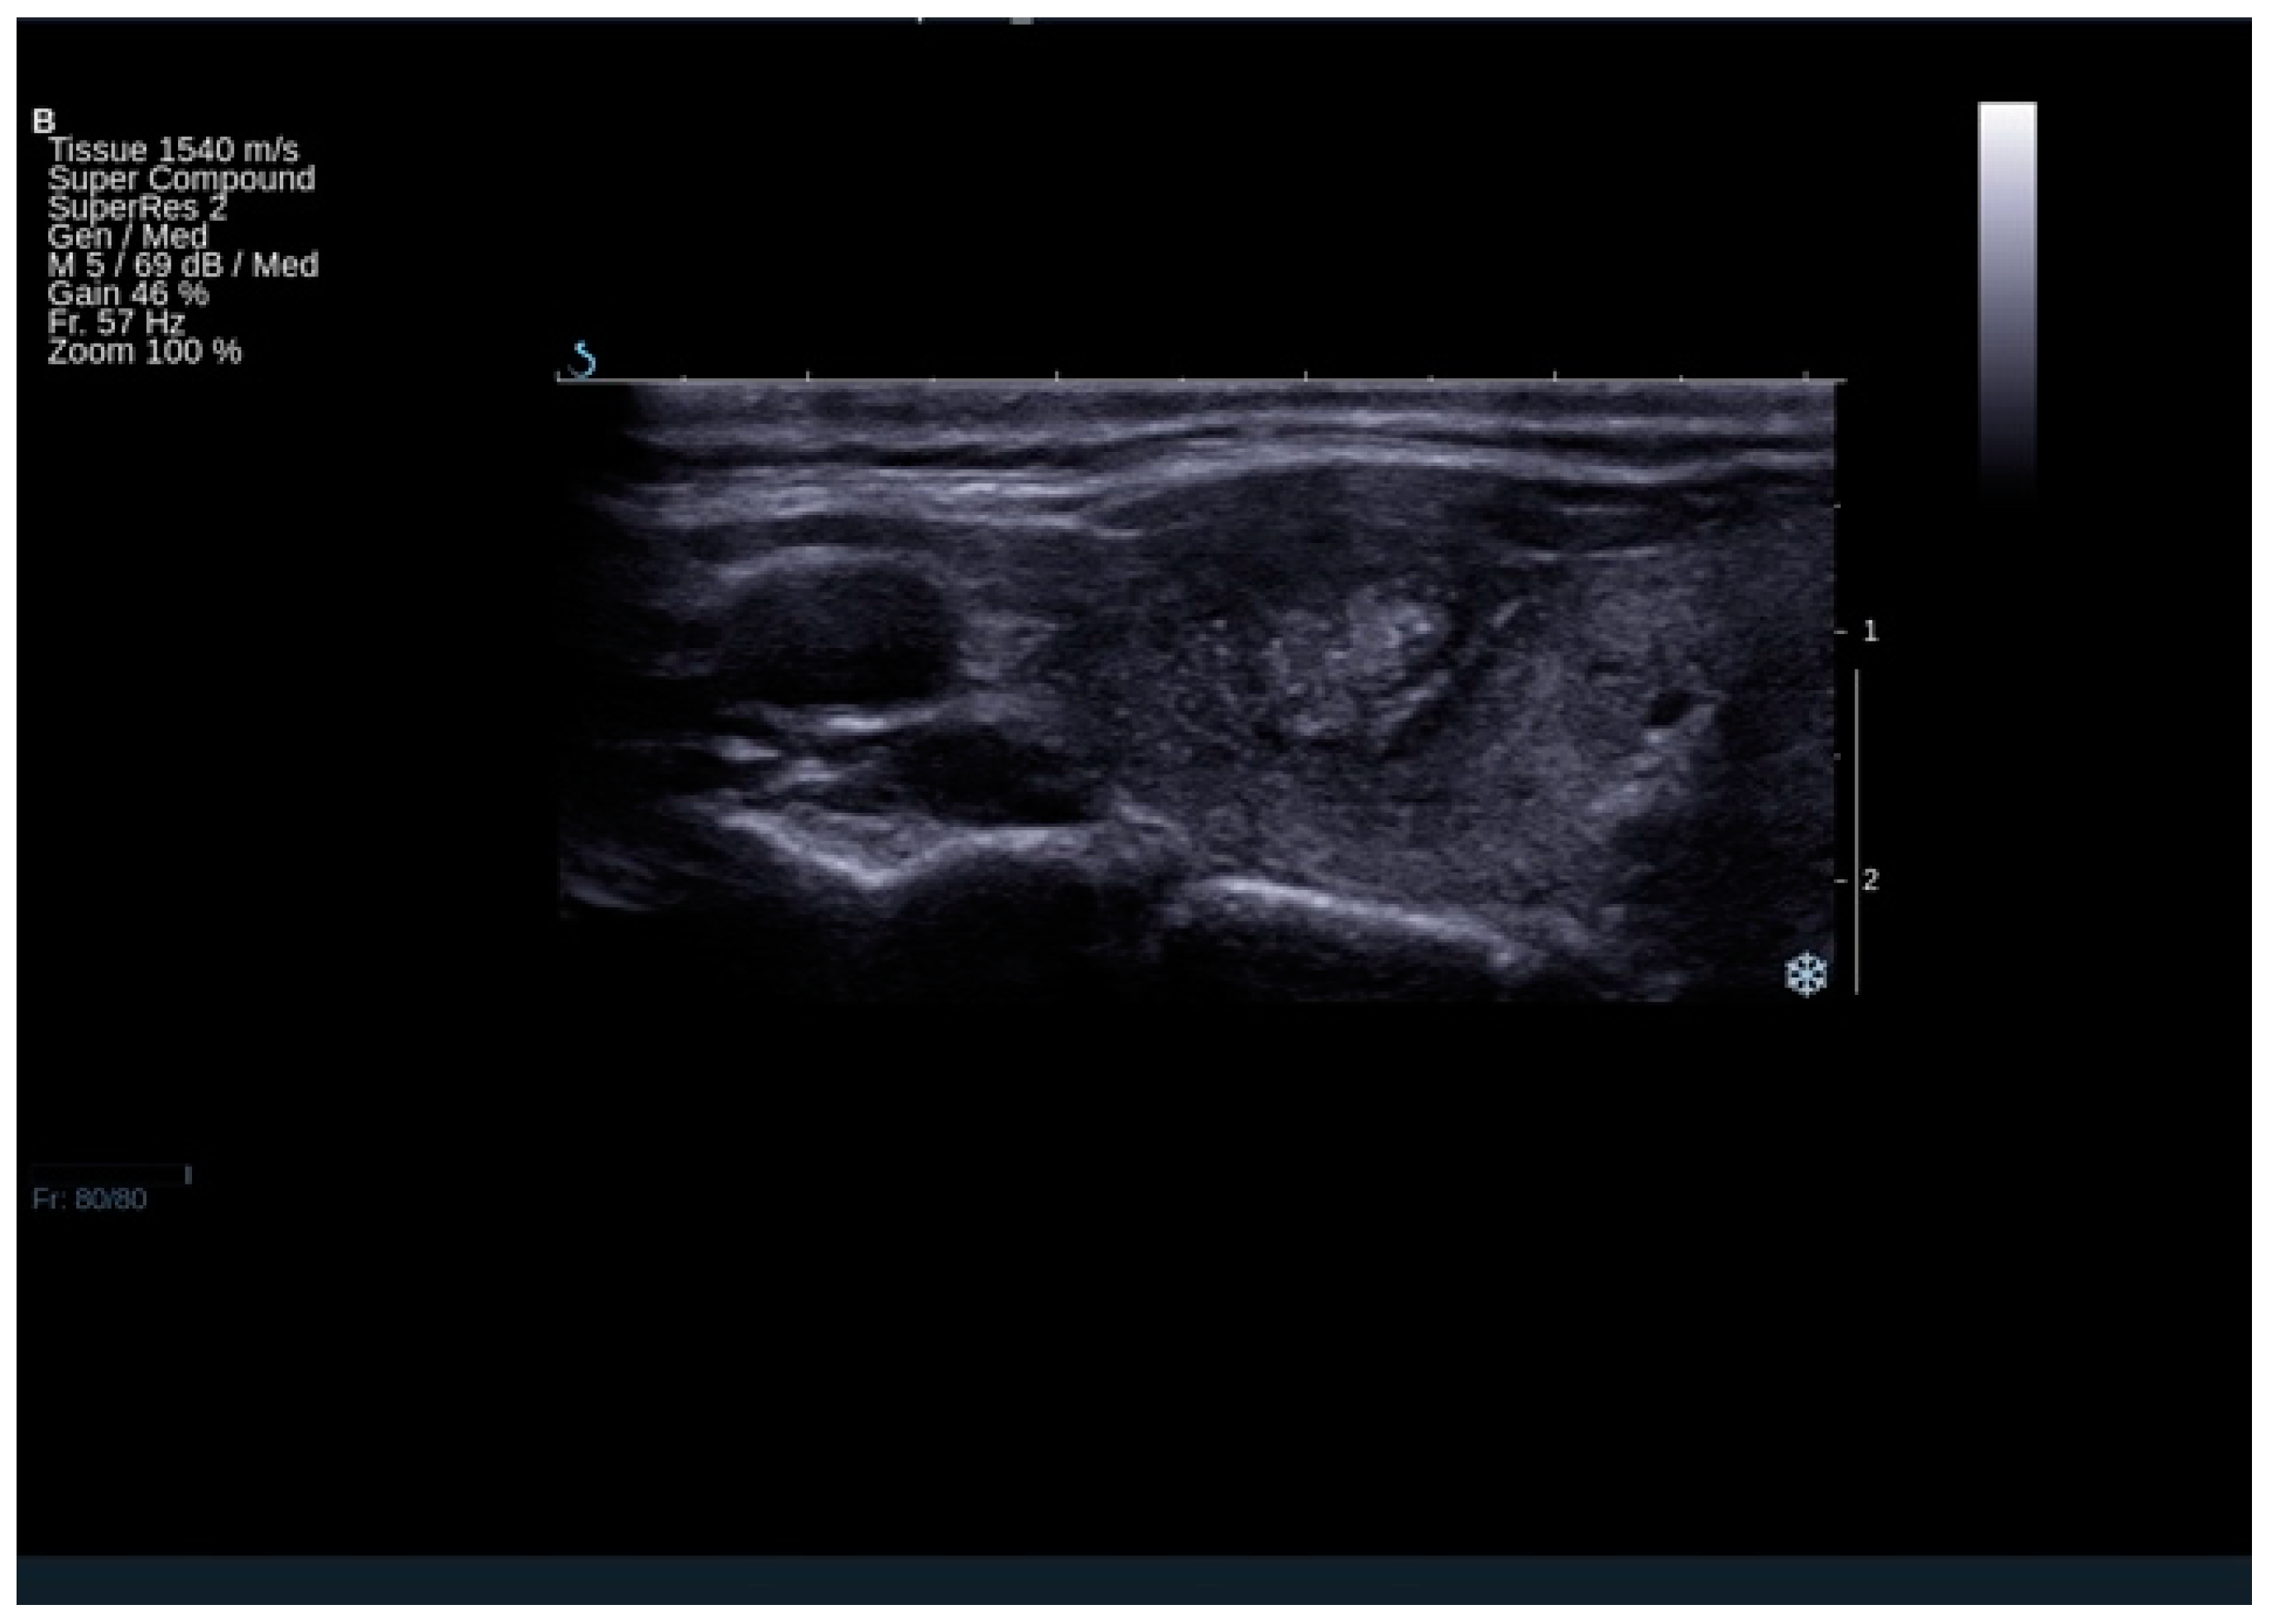

Patients finally diagnosed with FTC were more than 10 times more likely to have a tumor protrusion (Figure 3)—OR (95% CI): 10.19 (2.62–39.71) (Tables S2 and S13a,b). The analysis included 633 patients and the group proved to be homogenous (test for heterogeneity: I2 = 0.0%, p = 0.4350. The specificity (95% CI) of this feature reached 1.00 (0.99–1.00) with low sensitivity (95% CI) of 0.06 (0.03–0.09).

Figure 3.

The result of ultrasound examination demonstrating thyroid lesion, which turned out to be follicular cancer on histopathological examination. The lesion presents tumor protrusion, irregular margins, microcalcifications, and heterogeneous echostructure.

Our meta-analysis demonstrated that the sonographic feature the most strongly increasing the risk of FTC, but not underlined in the previous studies, was capsule protrusion. Although only two studies took into account this feature, it turned out to be the substantial differentiating factor between FTA and FTC, with an OR at the level of 10.19 [13,32]. Capsule protrusion towards the surrounding structures with or without visible capsule disruption can be considered as a risk factor for the extrathyroidal extension, which is equal to 61% in these subjects, while 31% for macroscopic invasion [40].